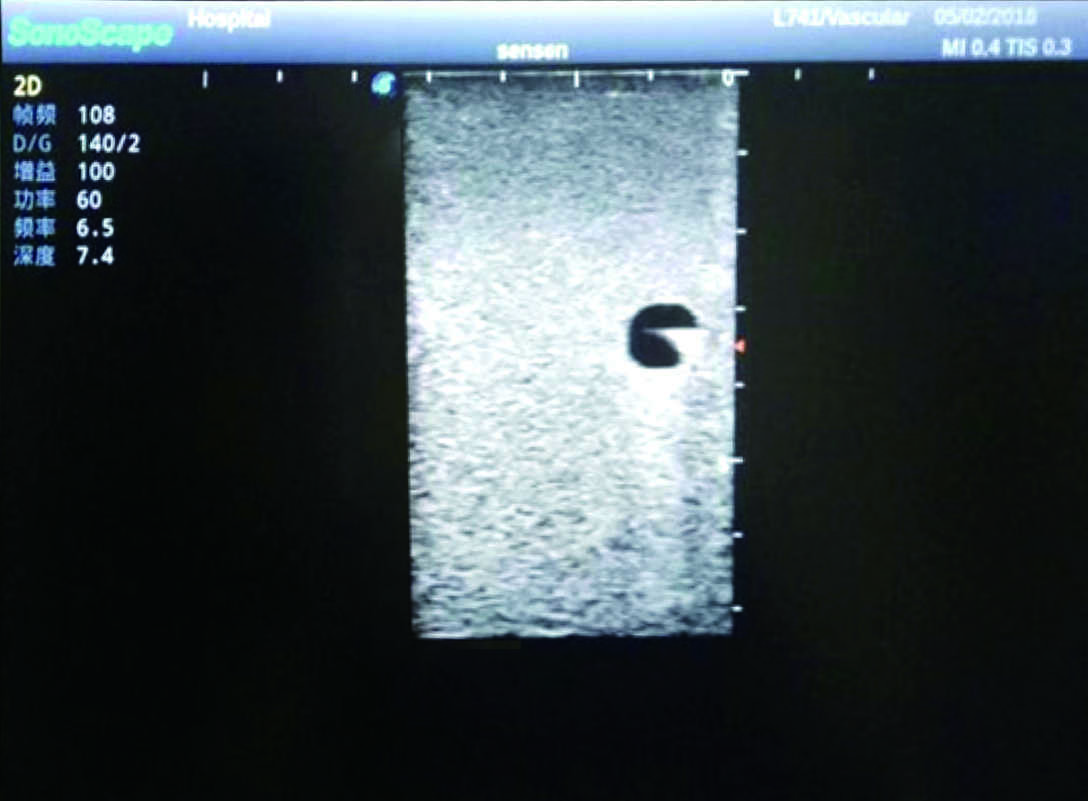

3)   Clear and real images of the tissues and organs (basilic vein and superior vena cava)